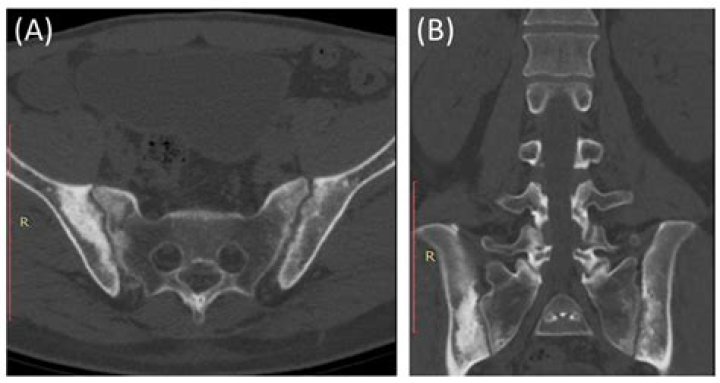

MRI lesions in the sacroiliac joints of patients with spondyloarthritis

Will a CT scan show sacroiliitis?

This study showed that abdominal CT can establish a diagnosis of structural sacroiliitis with the same level of sensitivity but with a higher specificity (100%) than pelvic plain radiography.